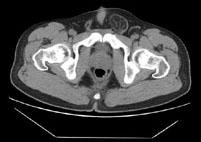

男,29岁,因左腹股沟突发痛性肿物3小时入院,左腹股沟皮下环处有一约4cm×5cm的肿物,触痛甚,质软,基底部有一细蒂,左阴囊发育小,睾丸缺如,CT检查如...

问题 男,29岁,因左腹股沟突发痛性肿物3小时入院,左腹股沟皮下环处有一约4cm×5cm的肿物,触痛甚,质软,基底部有一细蒂,左阴囊发育小,睾丸缺如,CT检查如图所示,下列说法错误的是 ( )

选项 A、腹股沟斜疝 B、左腹股沟区肿块为曲张的精索静脉 C、精索静脉曲张 D、腹股沟直疝 E、左睾丸下降不全

答案 D